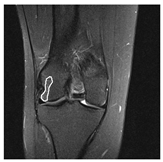

| Patient | Patient ID | Image Label | Image Prediction | Original Image | High Intensity Masking Image |

|---|---|---|---|---|---|

| Edema | 21 | Edema | Non-edema | ![]() | ![]() |

| Edema | 21 | Non-edema | Edema | ![]() | ![]() |